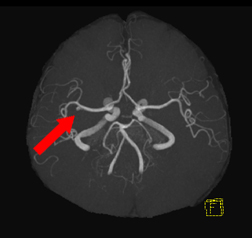

脳動脈瘤